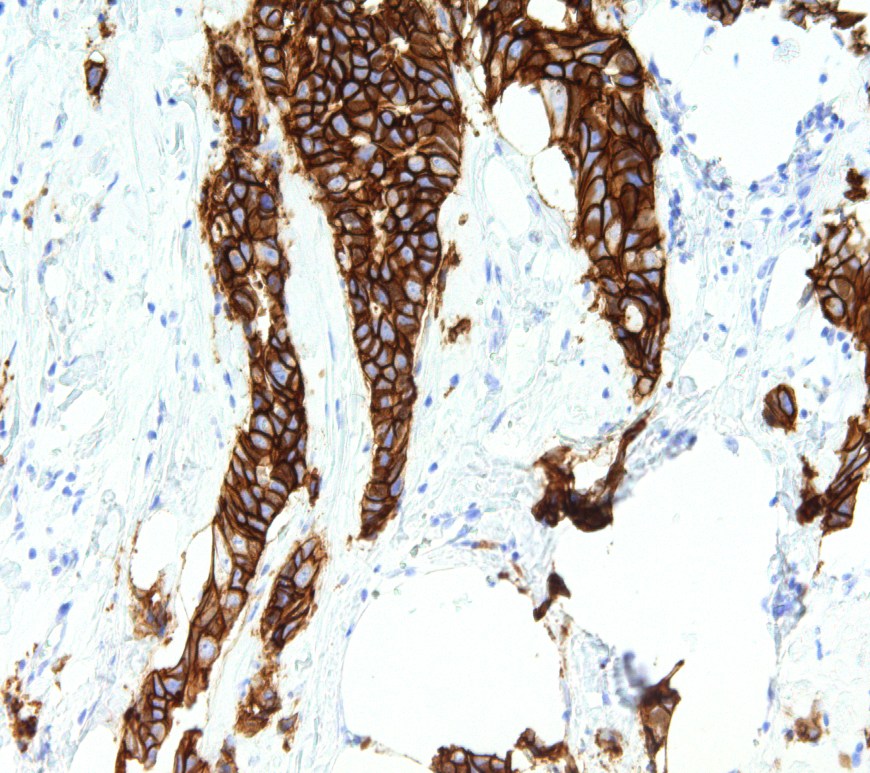

Author: Kimberly Johnston ’26 Endometriosis is defined by the growth of endometrial tissue outside the uterus where it does not belong. It occurs in about 10% of women of reproductive age and leads to chronic pelvic pain and infertility. Despite the prevalence of this disease, its cause remains unknown. While there is no known cure to endometriosis, there are methods of symptom management, including hormone … Continue reading Exploring the Therapeutic Potential of Melatonin in Endometriosis Management